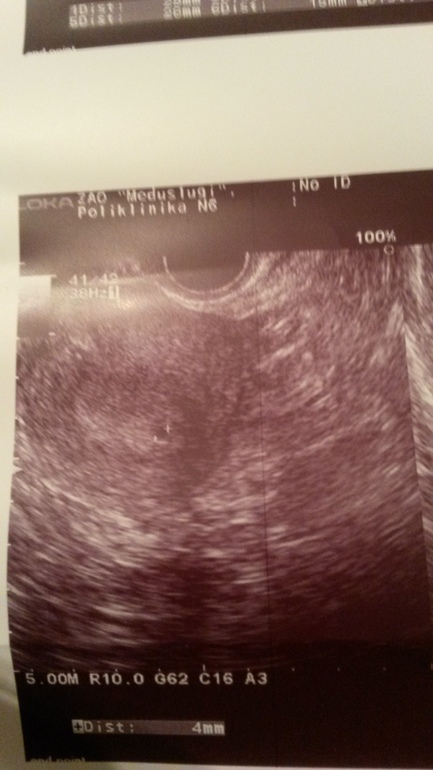

Дописываю:Чуда не произошло, утром пришли месячные(( 23 ДЦ, пошла на узи перед постановкой на учет в кабинет по невынашиванию (была ЗБ в июле) результат меня удивил. Фото прикрепляю. Тест девственно чист. Признаков беременности никаких нет.

На фото действительно на пя похоже...но тут недавно уже был случай. Может хгч сдать?

Девочка если не ошибаюсь тоже на узи поставили беременность а хгч 0. Переделала узи нет бер.

У меня такое было перед последними мес.Видимо,эндометрий уже начал отходить.А у вас пусть это будет б.!

Да, я поняла, что ещё только 23 дц. И поэтому странно, что уже увидели т.к. при задержке бывает, что не видят. Если только О была очень ранняя.

Ничего себе!!! Чудеса!!! Может сдать кровь на хгч? Обычно на узи видят срок от 5 недель, при задержке М На 5-7 дней.